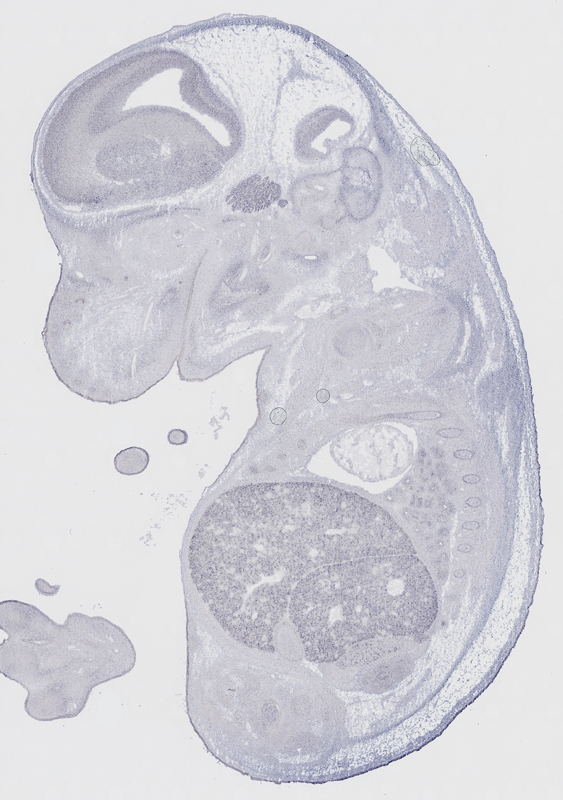

Reference: J:153498 Diez-Roux G, et al., A high-resolution anatomical atlas of the transcriptome in the mouse embryo. PLoS Biol. 2011;9(1):e1000582

Assay type: RNA in situ

Gene symbol: Cisd1

Gene name: CDGSH iron sulfur domain 1

Specimen euxassay_003163_01: embryonic day 14.5 (more )

TS23: liver lobe Weak Regionally restricted euxassay_003163_01

TS23: trigeminal ganglion Weak Regionally restricted euxassay_003163_04

TS23: facial ganglion Weak Regionally restricted euxassay_003163_04

TS23: liver lobe Weak Regionally restricted euxassay_003163_04